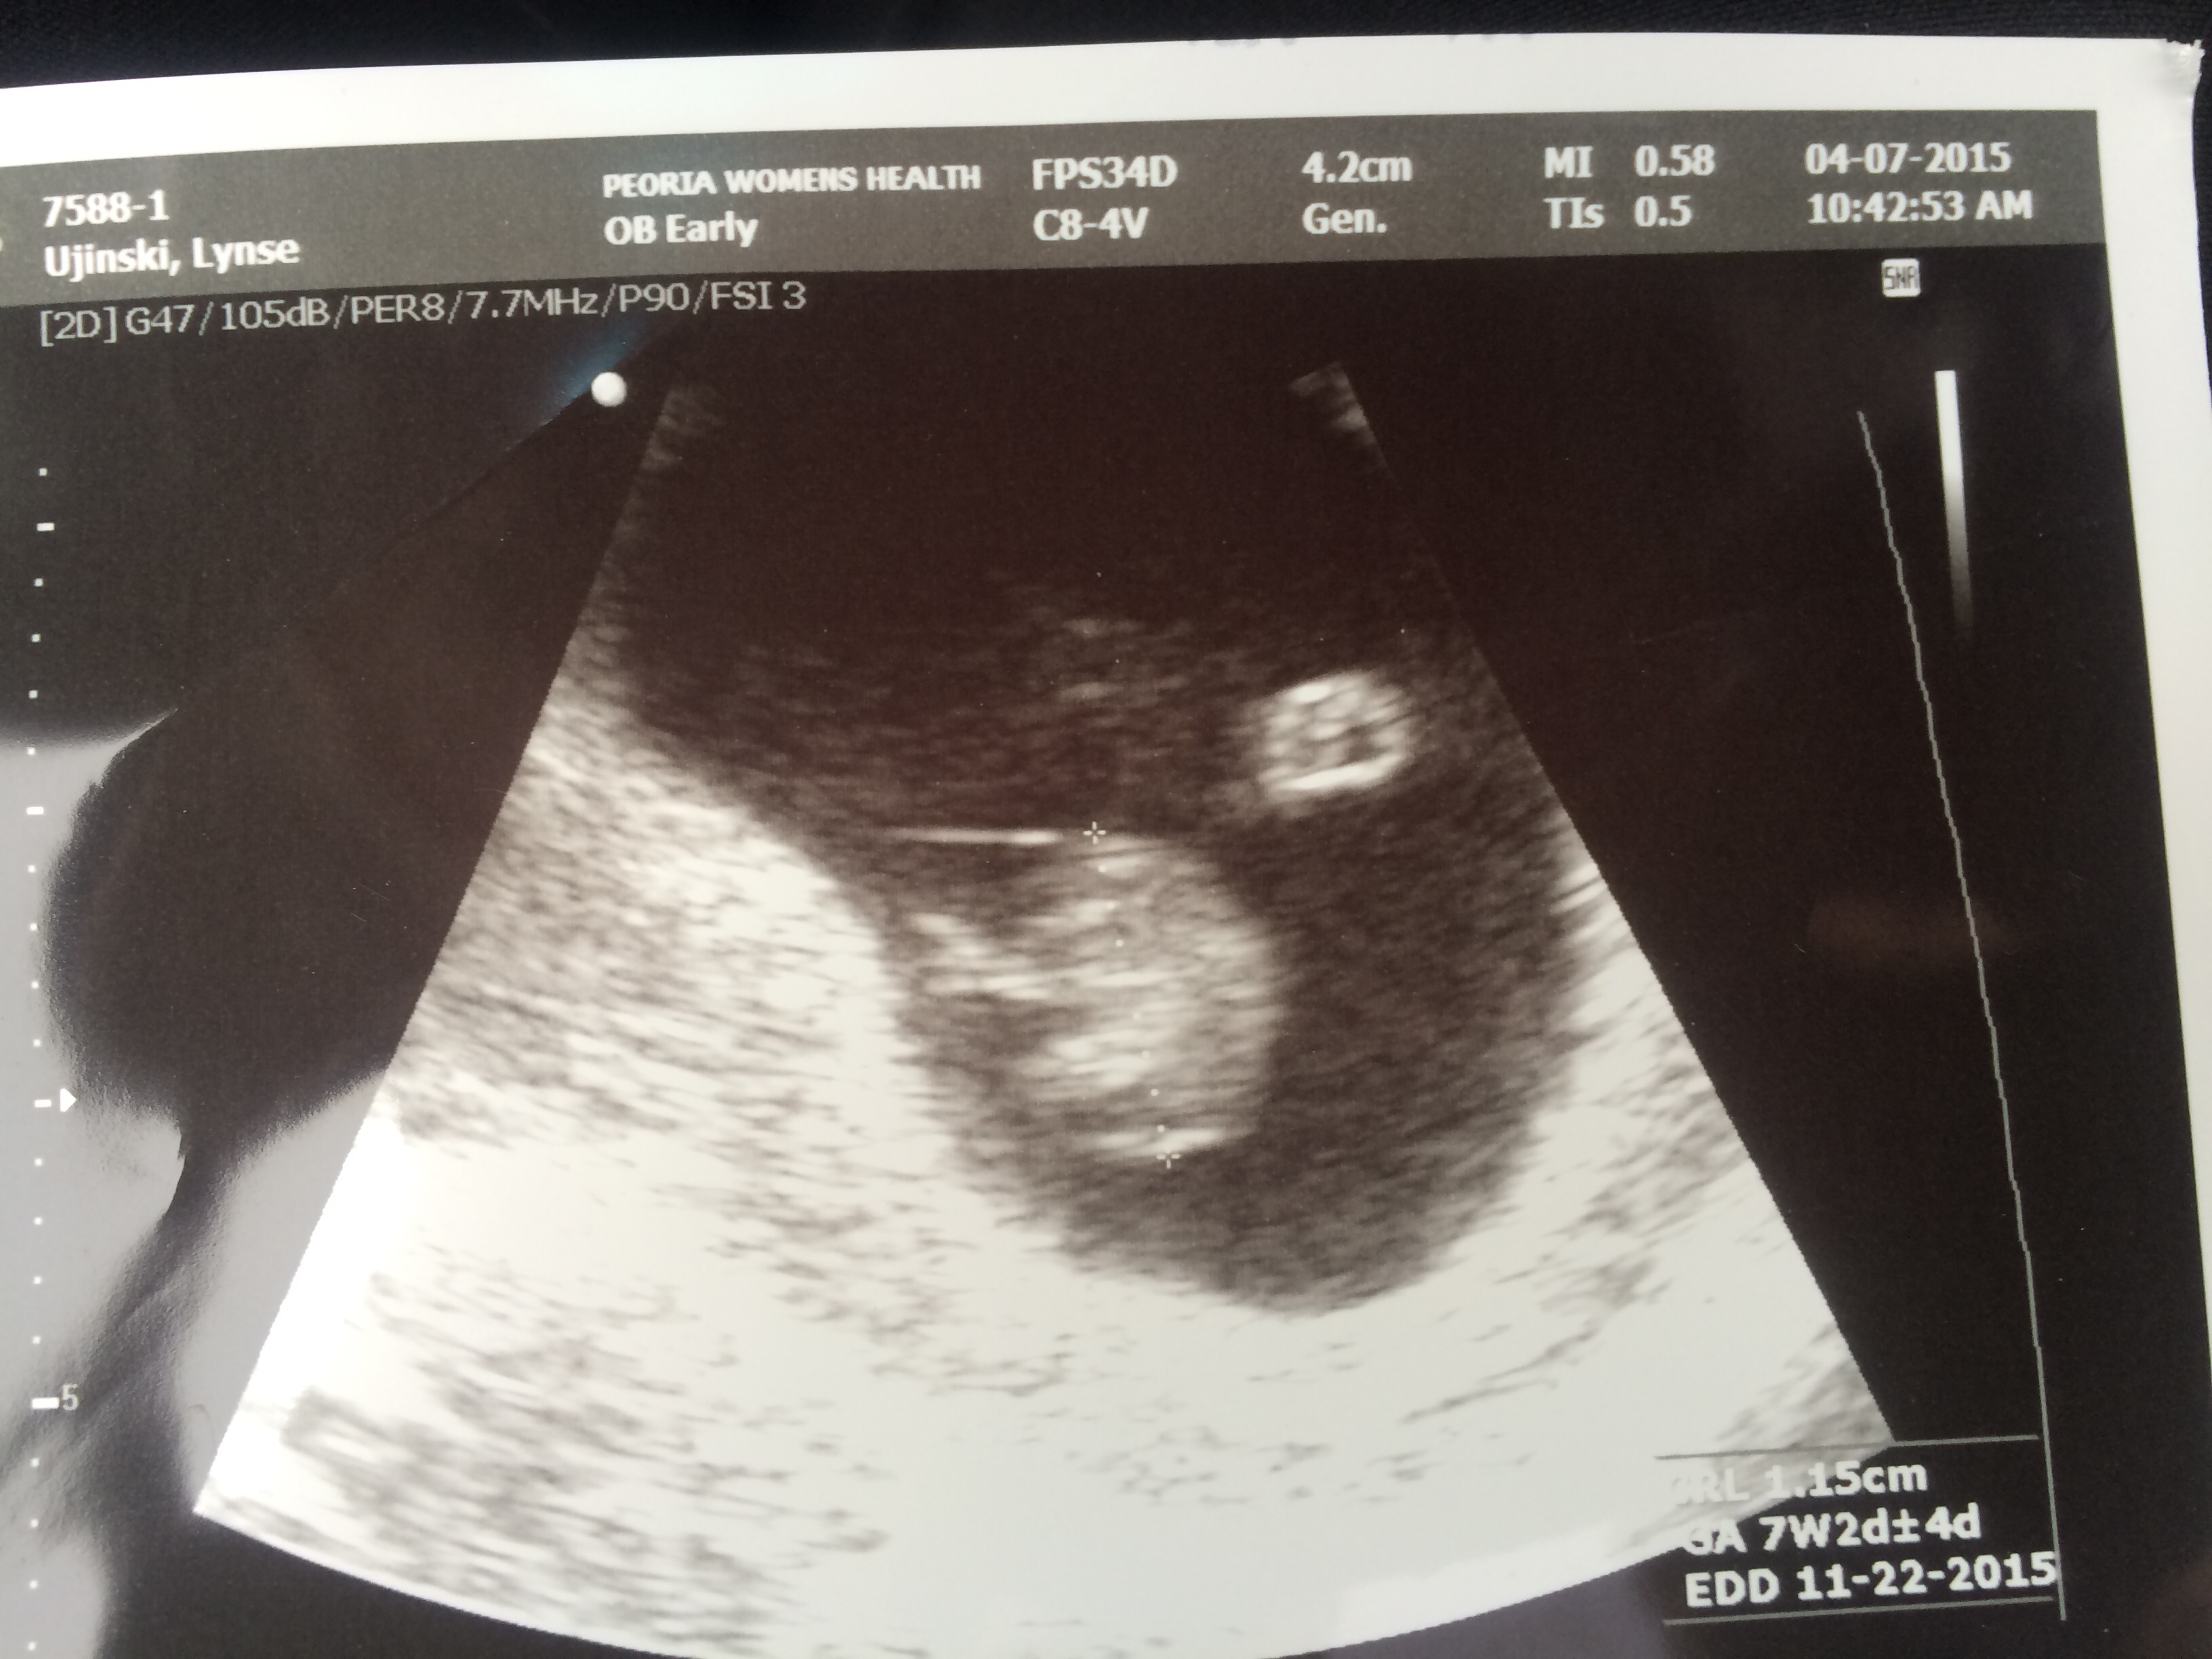

Had another u/s done yesterday due to some bleeding during sex. Baby is great and right on schedule 7 weeks 2 days...can't wait for my next one on the 29th!!